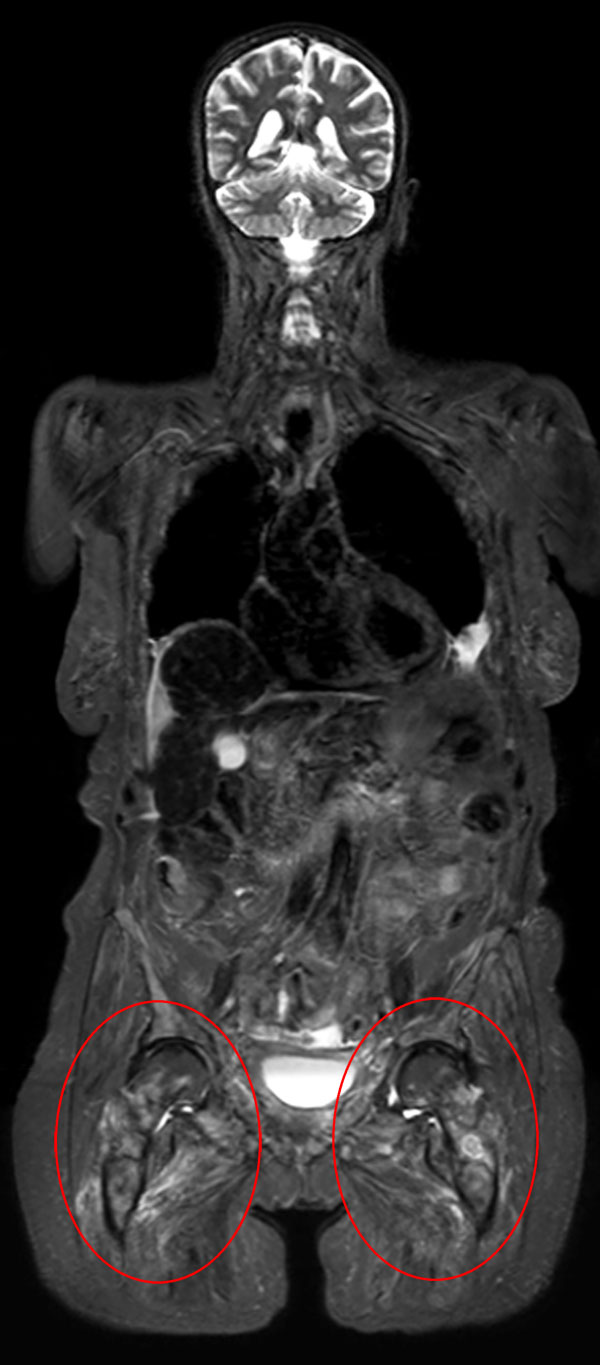

Patient with bone lesions.